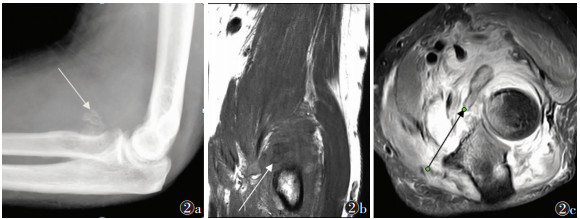

中期病变23例,X线(23例)、CT(16例)、MRI(12例)及SPECT/CT(4例)阳性率均为100.0%。X线或CT表现为软组织肿块周边高密度骨化影,14例呈絮状、片状或点状(图 1,2a,3a),9例呈蛋壳样骨化,肿块中央密度较低(图 4)。MRI示肿块呈分层状改变,最外侧(外层)呈条带状T1WI高信号、T2WI低信号(骨化);中间区(中间层)T1WI呈等信号、T2WI呈高信号;中心区域(内层)T1WI、T2WI均呈高信号;肿块外围呈边界不清的T2WI和STIR脂肪抑制高信号(水肿)(图 2b,2c)。SPECT/CT表现为病灶整体显像剂摄取,病灶中央摄取程度高于周围(图 3b)。

| 图 2 男,32岁,右侧肘关节骨化性肌炎(中期) 图 2a DR侧位图像,显示肘关节前侧环形骨化(箭头处) 图 2b,2c 分别为MRI T1WI冠状位、T2WI STIR横轴位图像示肘关节前侧软组织内双低信号影,呈环形分布(箭头),周围软组织弥漫性水肿信号影 |

3.2 中期外伤后5~8周,病理上出现骨化,从病灶外周向中央发展,呈蛋壳样表现,可呈典型的3层表现,但较少见;临床表现为发热、局部肿块及压痛;影像表现为肿块周围逐渐出现骨化。本研究中此期患者X线、CT、MRI及SPECT/CT显像均为阳性。有研究[9]显示蛋壳样骨化是其特征影像表现,但本研究仅39.1%(9/23)出现此特征。MRI可呈典型3层表现,外层为骨化层,中间为萎缩肌纤维层,内层为出血层。关于核医学在骨化性肌炎的应用报道,多为个案报道,且病例均为中期,病灶显像剂异常摄取[10-13]。本研究中期骨化性肌炎SPECT/CT表现为病灶整体显像剂摄取,病灶中央摄取程度高于周围,提示骨化性肌炎是一种渐进的成骨过程,且从周围向中央进展。